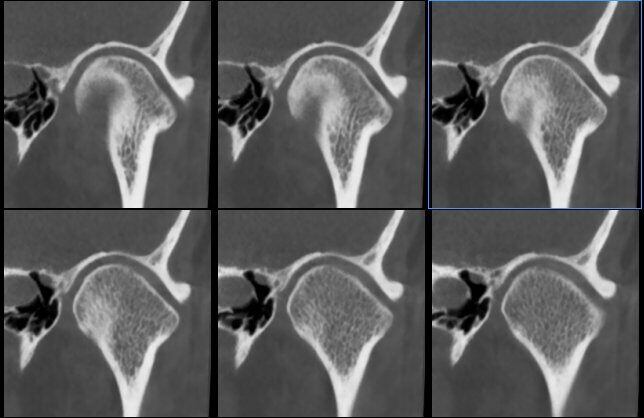

ATM Bocca Chiusa